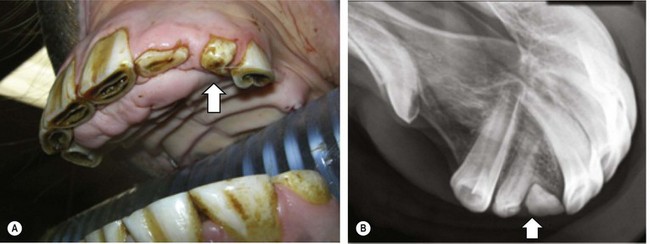

image image

Fig. 8.8 (A) Intra-oral radiograph of a premaxilla containing two bent, supplemental supernumerary (permanent) incisors lying at oblique angles, that have caused overcrowding and displacement of the remaining incisors. (B) One of these supernumerary incisors is visible, abnormally protruding at an oblique angle between 201 and 202.

Because of their normal morphology, supplemental supernumerary incisors can readily be confused with retained deciduous incisors. This is particularly the case with larger retained incisors, whose permanent successors erupted beside, rather than beneath, the deciduous incisor, and thus have not caused any resorption or mechanical displacement of the apex or reserve crown. Radiography usually distinguishes between a retained deciduous and supernumerary incisor, as a retained deciduous incisor is shorter and narrower than a supernumerary permanent incisor (see later), in contrast to supernumerary incisors that are usually of similar size (Fig. 8.8). Supernumerary incisors may cause overcrowding and displacement of the normal permanent incisors, and diastemata often occur beside the displaced incisors. A rostrally displaced supernumerary incisor may also develop between, and so cause separation of the normal incisors (Fig. 8.7).

Supernumerary incisors and possibly displaced normal incisors can erupt in an overcrowded manner along the normal incisor arch, and caudal (palatal) to them on the rostral aspect of the hard palate. In addition to the difficulty in clinically differentiating supplemental supernumerary incisors from normal incisors, it is usually very difficult to extract such displaced supernumerary incisors without causing damage to the remaining incisors, the hard palate and overlying soft tissues. Lateral and intra-oral radiographs generally demonstrate the great length of the reserve crowns of both the normal and the (indistinguishable) supernumerary incisors that are lying closely together, sometimes in an intertwined manner (Fig. 8.8). As the consequences of leaving multiple supernumerary incisors in are usually minimal, these teeth are, therefore, best not extracted. As the supernumerary incisors erupt, their occlusal surfaces are usually worn down by attrition – due to contact with food and intermittent contact with lower incisors due to the normal rostrocaudal movement of the mandible. If, however, supernumerary incisors are extremely displaced, individual teeth lose occlusal contact and overgrow. Such teeth should be reduced biannually, preferably using motorized equipment.